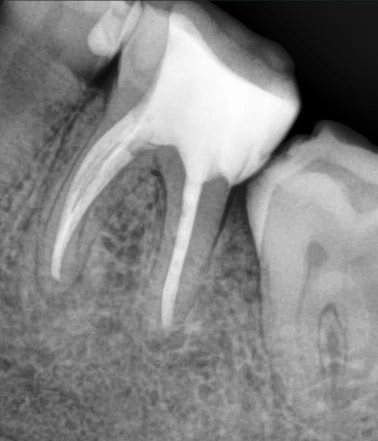

Пациент, обратился с жалобами на кровоточивость десен, неприятный запах изо рта. При осмотре был выявлен зуб, с негерметичной пломбой, провоцирующей застревание пищи и последующую кровоточивость десны. На рентгенологическом исследовании выявлен участок деструкции костной ткани. При снятии пломбы был неприятный запах из корневых каналов, что вызывало неприятный запах изо рта.

Проведено лечение зуба с использованием операционного микроскопа, лечение проходило в несколько этапов.

Через 6 месяцев после начала лечения наблюдалось значительное улучшение: уменьшение очага поражения и восстановление состояния десны. Рентгенологические исследования показали признаки регенерации костной ткани.